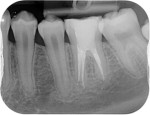

Post removal cases

Premolar retreatment